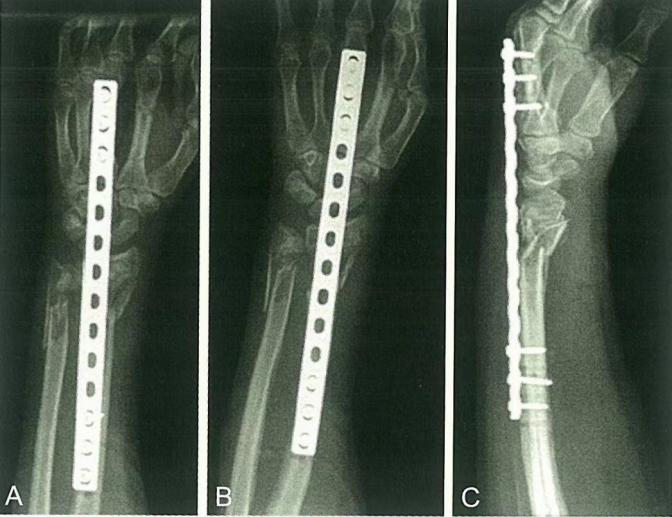

Случай ②